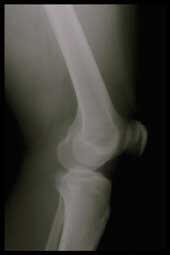

Arthrite et polyarthrite Rhumatoïde

Dans l'arthrite comme dans la polyarthrite rhumatoïde, la destruction du cartilage et de l'os semble principalement due à l'action d'une matrice d'enzymes (les métalloprotéinases)

qui incluent les collagénases et les stromélysines. Ces enzymes sont sous le contrôle de cytokines comme l'IL-1 ou le TNF-a particulièrement actives dans ces deux pathologies inflammatoires des articulations. Certaines enzymes ont des caractéristiques pro-inflammatoires, d'autres ont des propriétés anti-inflammatoires. La variation de l'équilibre entre ces forces intervient probablement dans les variations de l'activité de la maladie qui se réveille et s'apaise.